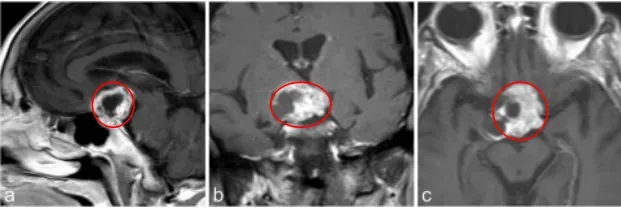

一位84岁的女性出现了视力下降的症状。经过检查,发现她双眼的视力均有减退,并且存在视野缺损。然而,对其进行内分泌评估后,结果显示其垂体功能保持完整。

a–c图中,MR成像显示鞍上部分实性,部分囊性对比增强病变,高度可疑的颅咽管瘤。